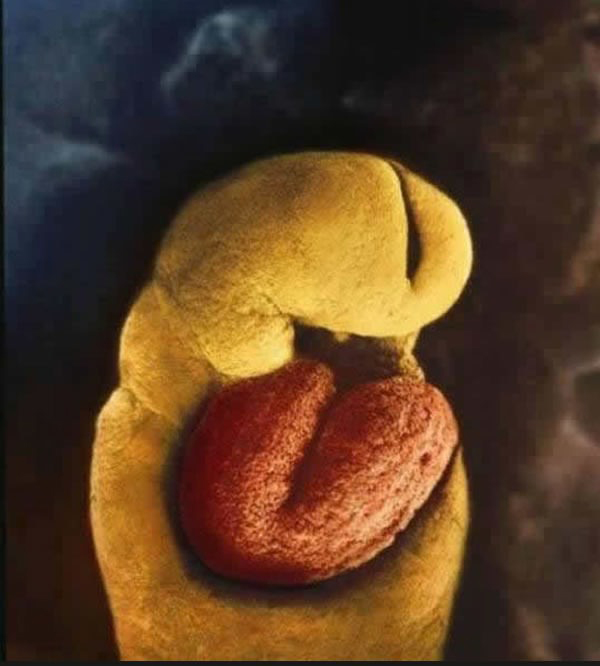

A svéd fotós, Lennart Nilsson, 12 évet töltött azzal, hogy képeket készített a magzatok méhen belüli fejlődéséről.

Csodálatos fotók készültek.

A 24. napon már dobog a szív

4. hét